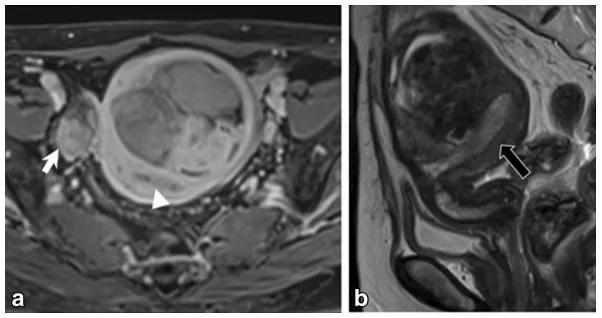

女,65 岁,左侧卵巢纤维瘤。图 a 箭头显示肿物 T2WI 呈低信号,DWI 未见明显扩散受限(b),增强扫描缓慢强化(c 增强早期,d 增强晚期)

女,70 岁,卵泡膜细胞瘤。图 a 增强扫描显示右侧卵巢肿物(白箭),同时子宫内膜增厚(图 a 白箭头及图 b 黑箭)。

女,32 岁,富于细胞性纤维瘤。右卵巢实性为主肿物,T2WI 稍高信号(图 a),DWI 高信号(图 b),增强扫描渐进行强化(c 增强早期,d 增强晚期)